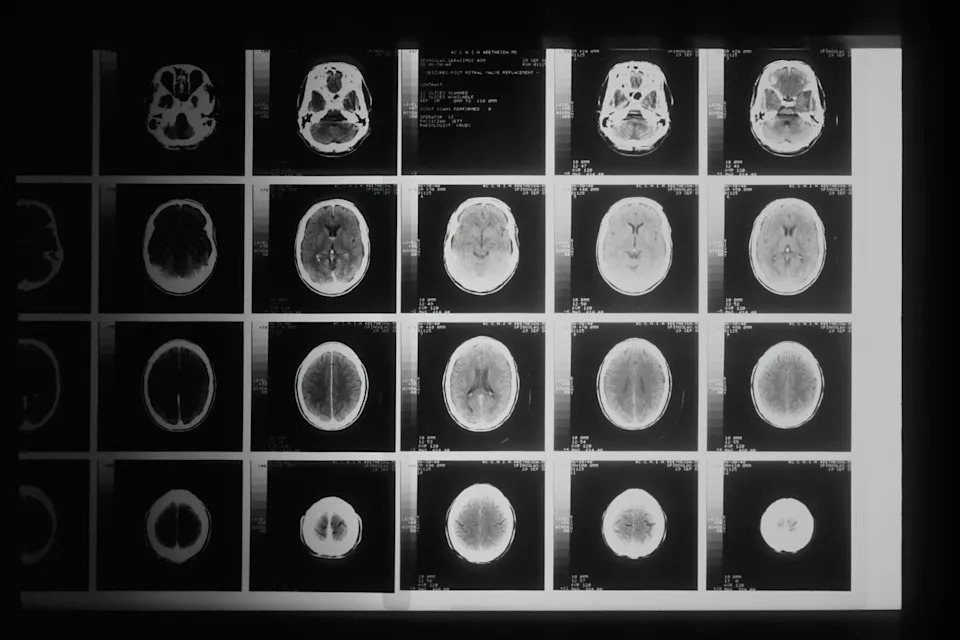

“Over a series of MRI scans, I watched as the tumor completely disappeared,” Grill said in an interview. Even more remarkably, the tumor has not returned since. Lucas, who is now thirteen, is considered officially cured of DIPG.